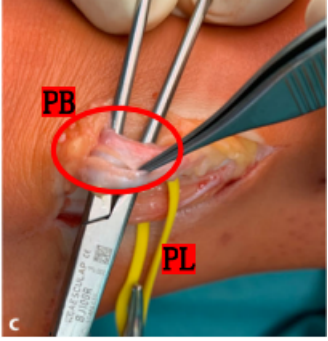

Raikin等学者提出将腓骨沟内腱鞘内半脱位不伴有腓骨上支持带损伤划为腓骨脱位的亚系。这些腱鞘内半脱位共有两型:

A型:腓骨肌腱无撕裂,肌腱暂时换位;

B型:腓骨短肌存在纵向撕裂,腓骨长肌腱自撕裂处半脱位。

(3)手术方法可分为以下5类:

如不合并其他病理改变,可将支持带和骨膜直接缝合于外踝骨质上。

SPR撕脱开放手术锚钉修复

大部分急性损伤可以使用直接缝合修复,对慢性损伤则需根据患者的具体病理改变选择,如单纯的支持带结构损伤,可以直接缝合修复。如果直接修复不够稳定,需用其他组织加强。如果腓骨外踝窝较浅时,就需要使用加深手术。